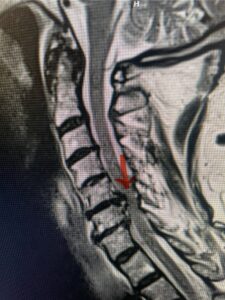

This 61-year-old female with a history of severe osteoporosis and a prior history of a laminectomy from l2-S1 with an L5-S1 instrumented fusion, presents with progressive low back pain and right lower extremity radiculopathy. MRI revealed a grade 1 L2-3 spondylolisthesis with severe stenosis mainly from severe right L2-3 facet joint hypertrophy which was compressing the right L3 descending nerve root. (Fig. 1). She had failed conservative management consisting of physical therapy and pain management with epidurals. She underwent an L1-3 revision laminectomy where we had to dissect a plane underneath the inferior aspect of the L2 lamina. We performed an instrumented fusion at L2-3 with special hydroxyapatite-coated screws to improve fixation to surrounding bone given here severe osteoporosis (Fig. 2) This worked out well and the patient had an uneventful recovery with relief of her leg pain.

Figures 1a: Sagittal and axial T2-weighted lumbar MRIs demonstrating a grade 1 L2-3 spondylolisthesis (red arrow) with severe stenosis secondary to right L2-3 facet hypertrophy (red arrow).

Fig 1b: Note the left L2-3 facet joint (blue arrow) is normal in size compared to the right (red arrow)